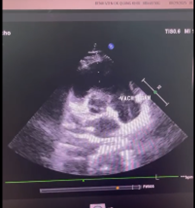

Hình ảnh Giant Eustachian Valve di chuyển trong buồng tâm nhĩ phải trên siêu âm tim của Chị Nguyễn T. V (mũi tên)

👉 Trong quá trình tầm soát, bác sĩ phát hiện chị mắc phải một dị tật bẩm sinh cực hiếm gặp trong buồng tâm nhĩ phải của quả tim, chỉ chiếm khoảng 0,2 % dân số thế giới – Quá phát van Eustachian (Giant Eustachian valve).